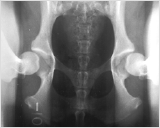

1. Distraktion

Die Hintergliedmaße des Hundes werden in einer neutralen, das Gelenk belastenden Position gelagert. Ein spezielles Instrument wird genutzt, um den angeborenen Spielraum der Hüfte festzustellen. Dieses PennHIP exklusive Verfahren erlaubt eine exakte, reproduzierbare Messung der "Lockerheit" der Hüfte